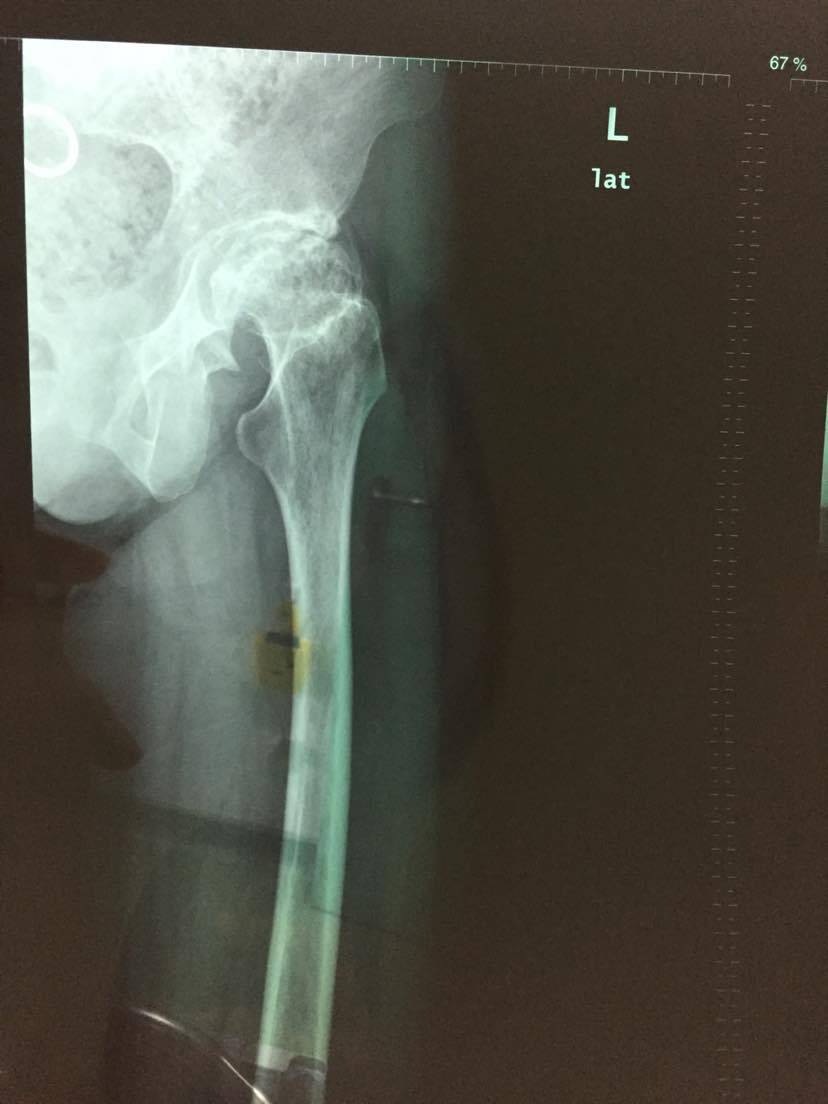

21天行动计划之三,髋关节置换住院第三天

早上教授过来巡查,昨天检查的结果都出来了。发两张重点的出来,自己身体的一部分,学着多了解一点,做什么检查都学着去看看。